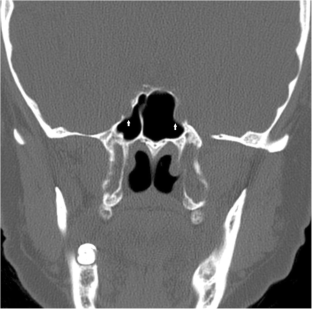

Fig. 2